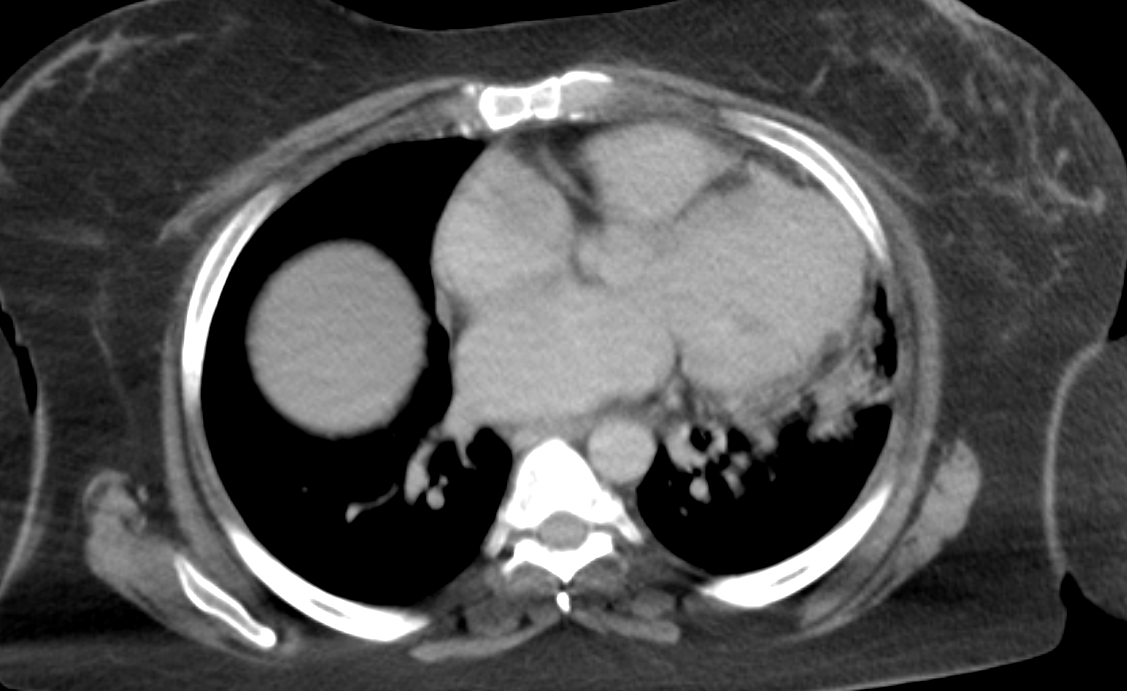

Quiz256: Anything? To sharp observers 👀 #radiology #medstaff #radres #meded